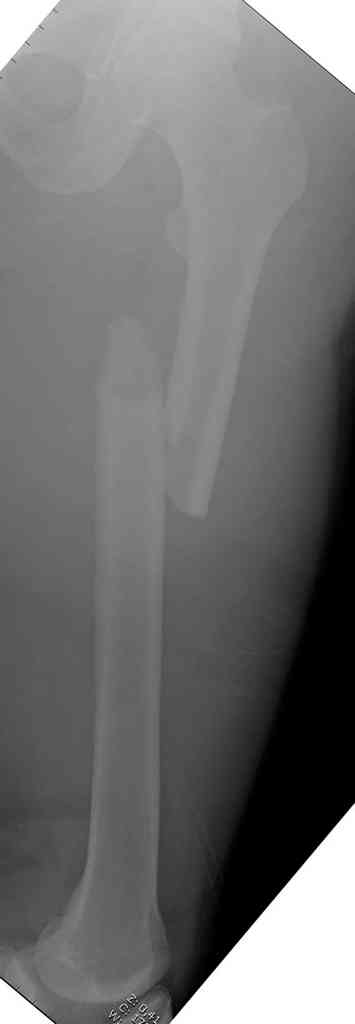

Здесь представлены снимки больного 65 лет, поступившего с диагнозом перелом

бедра после автоаварии.

В первый же день произведено антеградное штифтованием DePuy Trochanteric Nail.

На второй день (7) обнаружен пропущенный перелом,

и проведены шурурпы через и спереди штифта без удаления.

Послеоперационные снимки